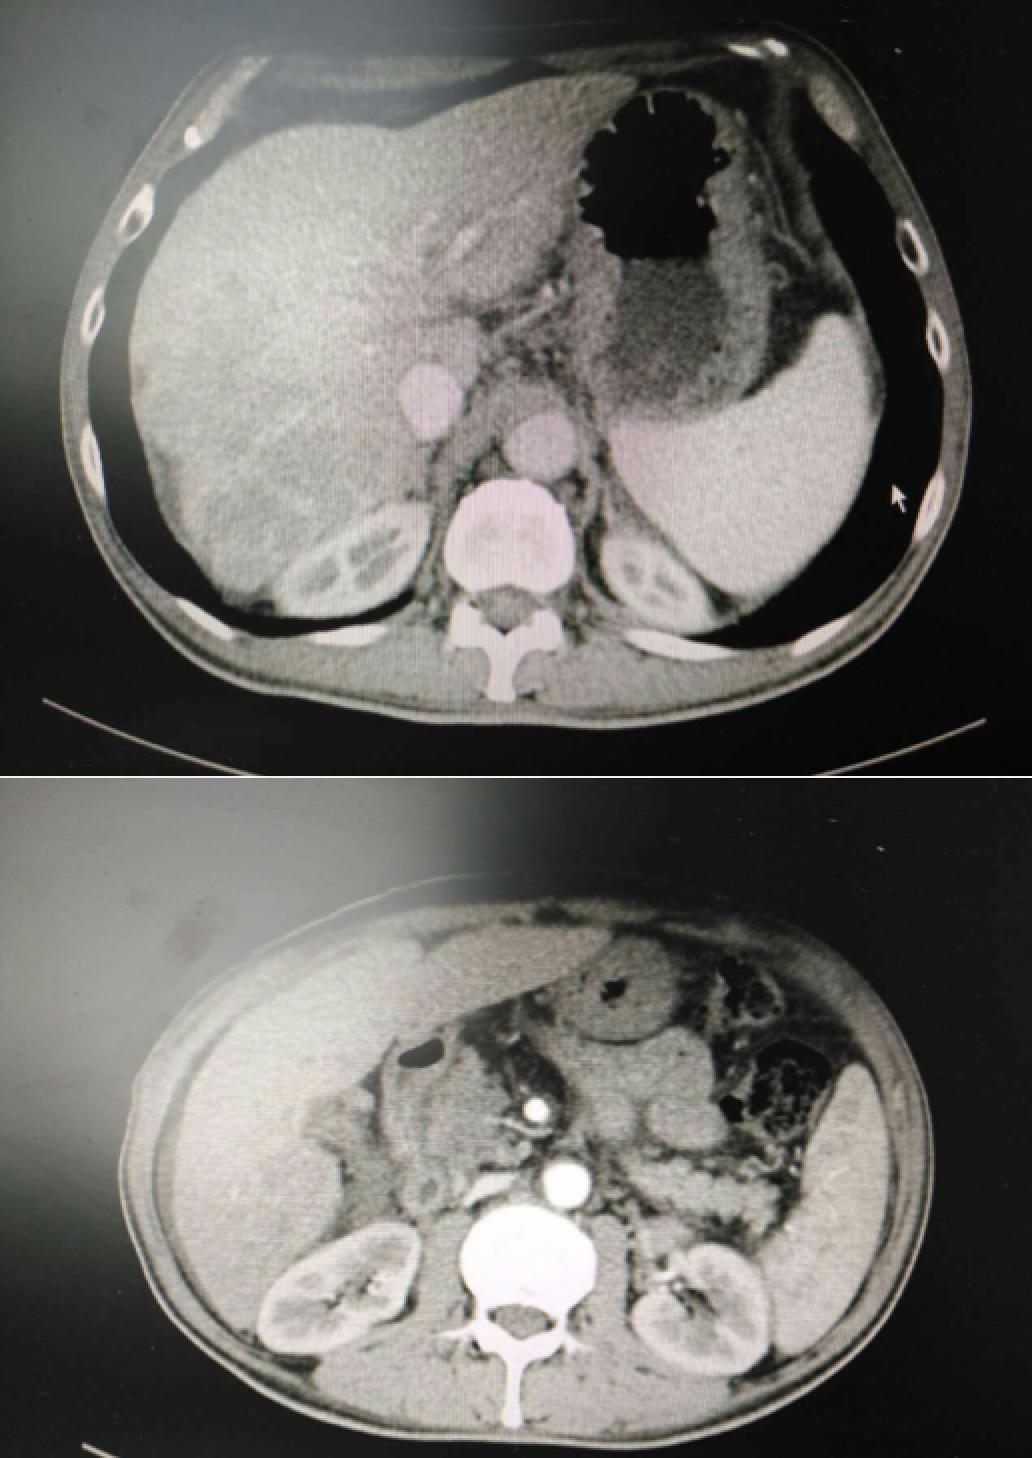

患者因纳差、烧心、腹痛、腹胀2月,于2016-01-17在某县人民医院行腹部CT示肝癌并门脉癌栓形成。分别于2016-01-22、2016-02-19于某市医院行两次TACE术(具体不详)。患者介入术后规律服用抗乙肝病毒、保肝、提高免疫力等药物治疗。2016-02-03至2016-04-30在某省立医院行5周期CIK免疫治疗。2016-05-18至2016-05-25于我院行射波刀治疗门静脉癌栓,具体放疗计划为:42Gy/7F。2016-06-24在我院行肝右动脉化疗栓塞术+肝右动脉灌注化疗术+间接门脉灌注化疗术,术中化疗总量,吡柔比星2mg、顺铂12mg、氟尿嘧啶250mg。分别于2016-05-10、2016-05-27、2016-06-13、2016-07-01、2016-07-27、2016-08-22、2016-09-19、2016-10-07、2016-10-19、2016-11-18、2016-12-18、2017-02-18行12周期免疫治疗。自2016-05-12起患者间断口服靶向药物阿帕替尼250-500mg/d,血压维持在220-130/95-70mmHg,血压升高期间伴上腹部不适,左侧为著,并向腰背部放射,偶尔反酸、烧心,剑突下疼痛,口服抑酸剂或进食后缓解,临床诊断为十二指肠溃疡,目前口服奥美拉唑、马来酸依那普利、氢氯噻嗪等药物对症降压。2017-03-02于我院行第二次肝右动脉化疗栓塞术+肝右动脉灌注化疗术+间接门脉造影术+肠系膜上动脉灌注化疗术。术中化疗总量,洛铂10mg、氟尿嘧啶500mg、吉西他滨400mg。目前间或皮下注射胸腺法新、重组人干扰素α-2b提高免疫力及慢性乙型病毒性肝炎治疗效果。

患者相关影像资料

4. 2017-3-15 DSA造影图中显示肿瘤组织血供一般,也未见癌栓显影,说明肿瘤组织或癌栓血供一般,也可能是靶向药物+栓塞化疗后,主要供血血管已闭塞,继续栓塞治疗效果有限。